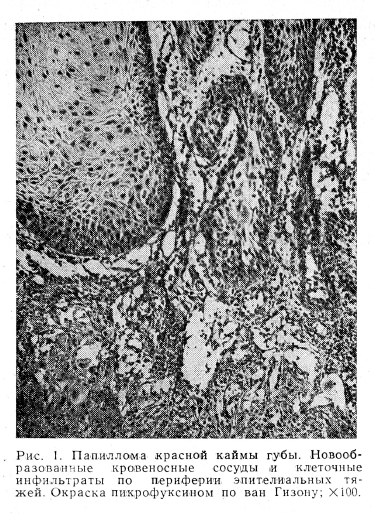

Все папилломы были фиброэпителиальными опухолями. Они состояли из соединительнотканной основы, имеющей вид разросшихся сосочков, покрытых эпителием. В соединительнотканных сосочках непосредственно на границе с эпителиальными тяжами кровеносные сосуды представлены щелевидной формы полостями, выстланными одним слоем эндотелиальных клеток, ядра которых выбухают в просвет сосудов и интенсивно закрашиваются по Фейльгену. Периваскулярная ткань при окраске по ван Гизону приобретает ярко-красный цвет, при импрегнации серебром дает нежную сеть аргирофильных волокон. Окраска толуидиновым синим при pH 4,8 выявляет слабую метахромазию; окраска препаратов по Мак-Манусу дает ШИК-положительную реакцию. Эластические волокна отсутствуют в тех участках препарата, где отчетливо определяется метахромазия, а плотность клеточных инфильтратов высока.

Стенки сосудов глубоко лежащих слоев стромы склерозированы и имеют разволокненную, местами выпрямленную эластическую мембрану (рис. 1).